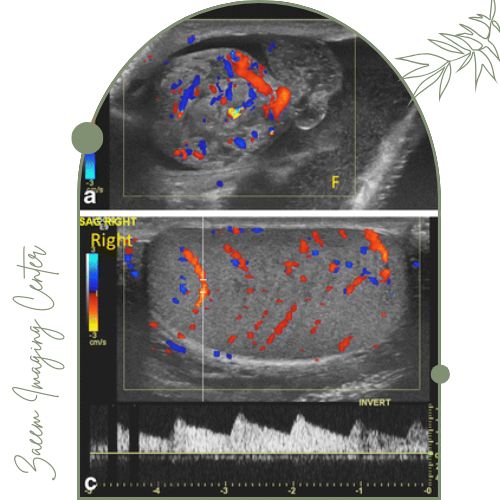

سونوگرافی بیضه یک روش تصویربرداری ساده و ایمن است که پزشک با استفاده از آن می‌تواند شرایط داخل بیضه را ببیند و اندازه، شکل و وجود هرگونه توده یا مشکل غیرطبیعی در را بررسی کند. سونوگرافی کالر داپلر نوعی پیشرفته‌تر از سونوگرافی معمولی است که علاوه بر نمایش ساختارهای داخلی بیضه می‌تواند جریان خون را هم به‌صورت رنگی نشان دهد.

تفاوت اصلی این روش با سونوگرافی ساده در این است که کالر داپلر به کمک یک فناوری ویژه (اثر داپلر)، سرعت و جهت خونرسانی عروق بیضه و اطراف آن را بررسی می‌کند و این جریان را با رنگ‌بندی روی مانیتور مشخص می‌سازد.